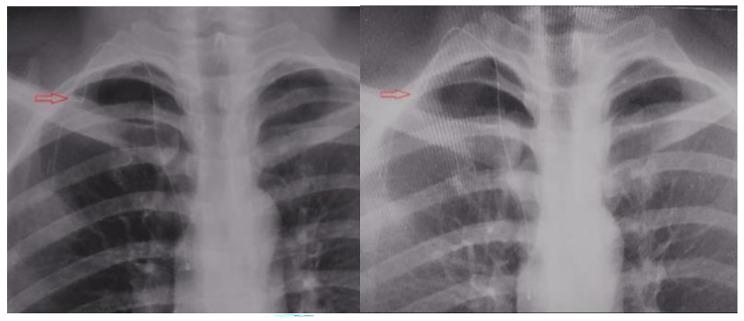

We analyzed 65 cases of TIVADs (chest wall) and 65 cases of PICC at the orthopedic department of the Fourth Hospital of Hebei Medical University between June 2019 and December 2021, which were diagnosed with malignant bone tumors or soft tissue tumors of the lower extremities (tumors had to be relatively sensitive to chemotherapy), received regular chemotherapy, with ≥ 14 cycles (42 weeks). The two groups were compared in terms of catheter indwelling time, catheter-related complications, Constant-Murley shoulder function score, and displacement of the position of the catheter end on the catheterization side.

Compared to the PICC group, at six months after catheterization, the TIVADs group reported better outcomes for catheter indwelling time, catheter-related complications, and Constant-Murley score for the catheterization-side shoulder joint (p < 0.05). The TIVADs group also reported less displacement of the catheter end position after 180° abduction of the catheterization-side shoulder joint (p < 0.05).